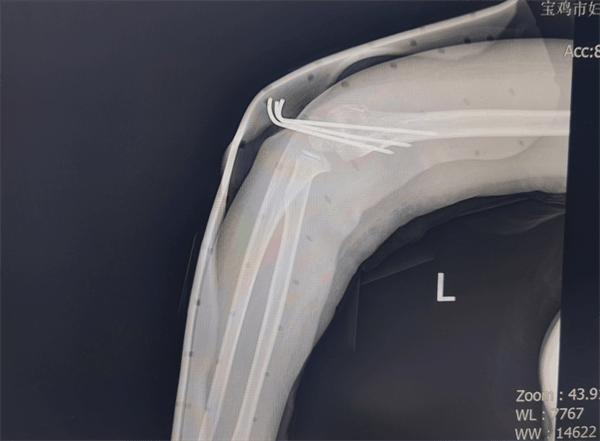

肱骨髁上骨折是儿童最常见的肘部骨折之一,手术治疗须兼顾骨折复位精度与骨骺(生长板)保护,直接关乎莹莹未来骨骼发育。莹莹的微创精准手术在全身麻醉下开展,手术团队在C臂透视机精准引导下,进行“毫米级”精细操作:无需大开刀口,仅通过皮肤外对抗牵引和手法复位,便将移位骨折端完美对合;随后将细如发丝的克氏针经皮穿入交叉固定骨折块,全程出血极少,并通过关节造影确认关节面平整。该微创术式最大程度降低了对周围软组织及骨骺的损伤,为莹莹远期功能完全恢复提供有力保障。

术后,莹莹返回小儿外科病房,在医护团队的精心照料下恢复迅速。术后三天复查X线显示,内固定位置完美,骨折对位线满意。1月7日,莹莹康复出院。出院时,医护人员详细告知家长家庭护理要点及功能锻炼方法,为莹莹后续恢复保驾护航。